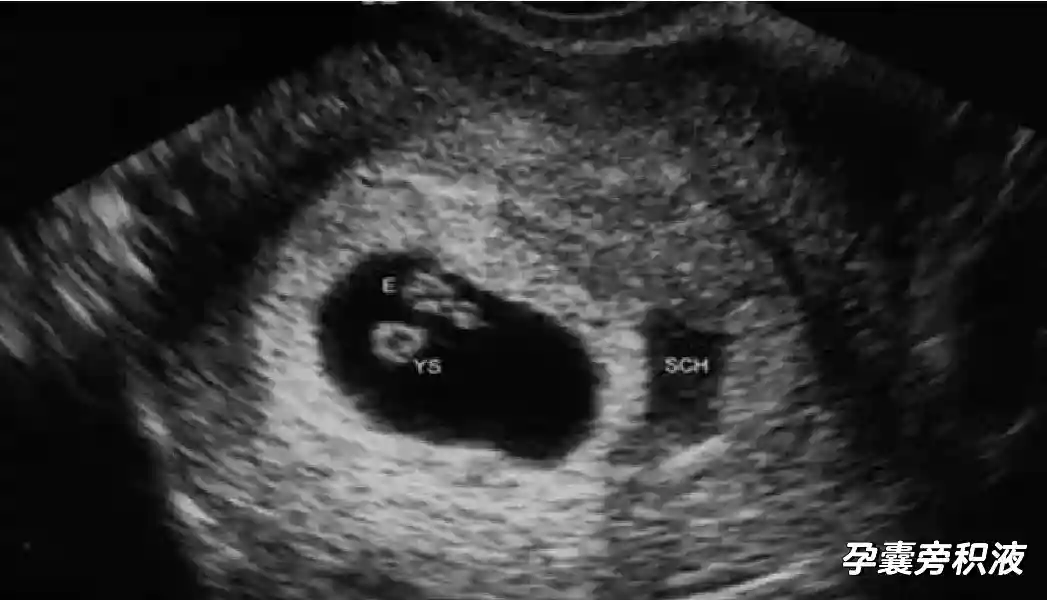

2??卵黄囊:是妊娠囊内第一个解剖结构,直径<7mm。表现为小环状,中央为无回声,囊壁薄,内透声好。卵黄囊位于胚胎旁胚外体腔内。卵黄囊通常在孕5-6周时出现,5-10周稳步增长,一般不超过7mm,至12周消失。妊娠囊的大小与卵黄囊之间有一定关系,妊娠囊平均直径> 8 mm 时,经阴道超声均应显示卵黄囊,妊娠囊平均直径> 18 mm 时,经腹超声均应显示卵黄囊。